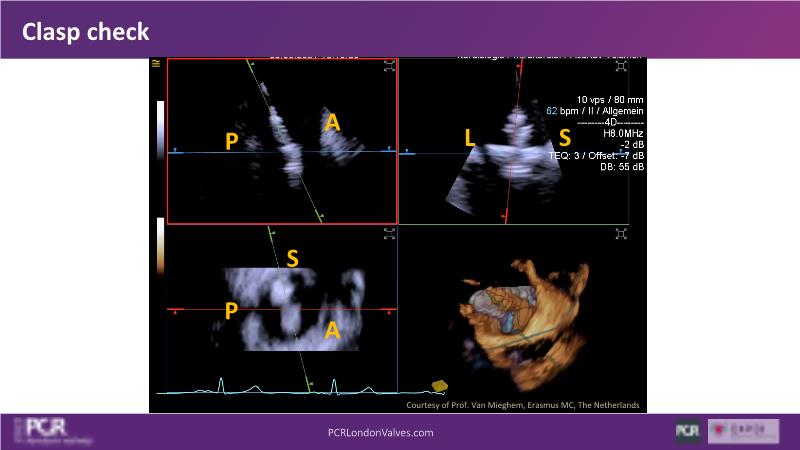

Expert roundtable: 4D ICE in tricuspid interventions

Join this session if you want to get familiar with the 4D ICE technology and the key elements of image guidance for tricuspid interventions, understand how 4D ICE can assist in specific procedural steps during challenging tricuspid interventions, and engage in an interactive discussion with experts about the current use of 4D ICE and insights into future developments.

- To get familiar with the 4D ICE technology and the key aspects of image guidance for tricuspid interventions

- To learn how 4D ICE can support specific procedural steps in challenging tricuspid interventions